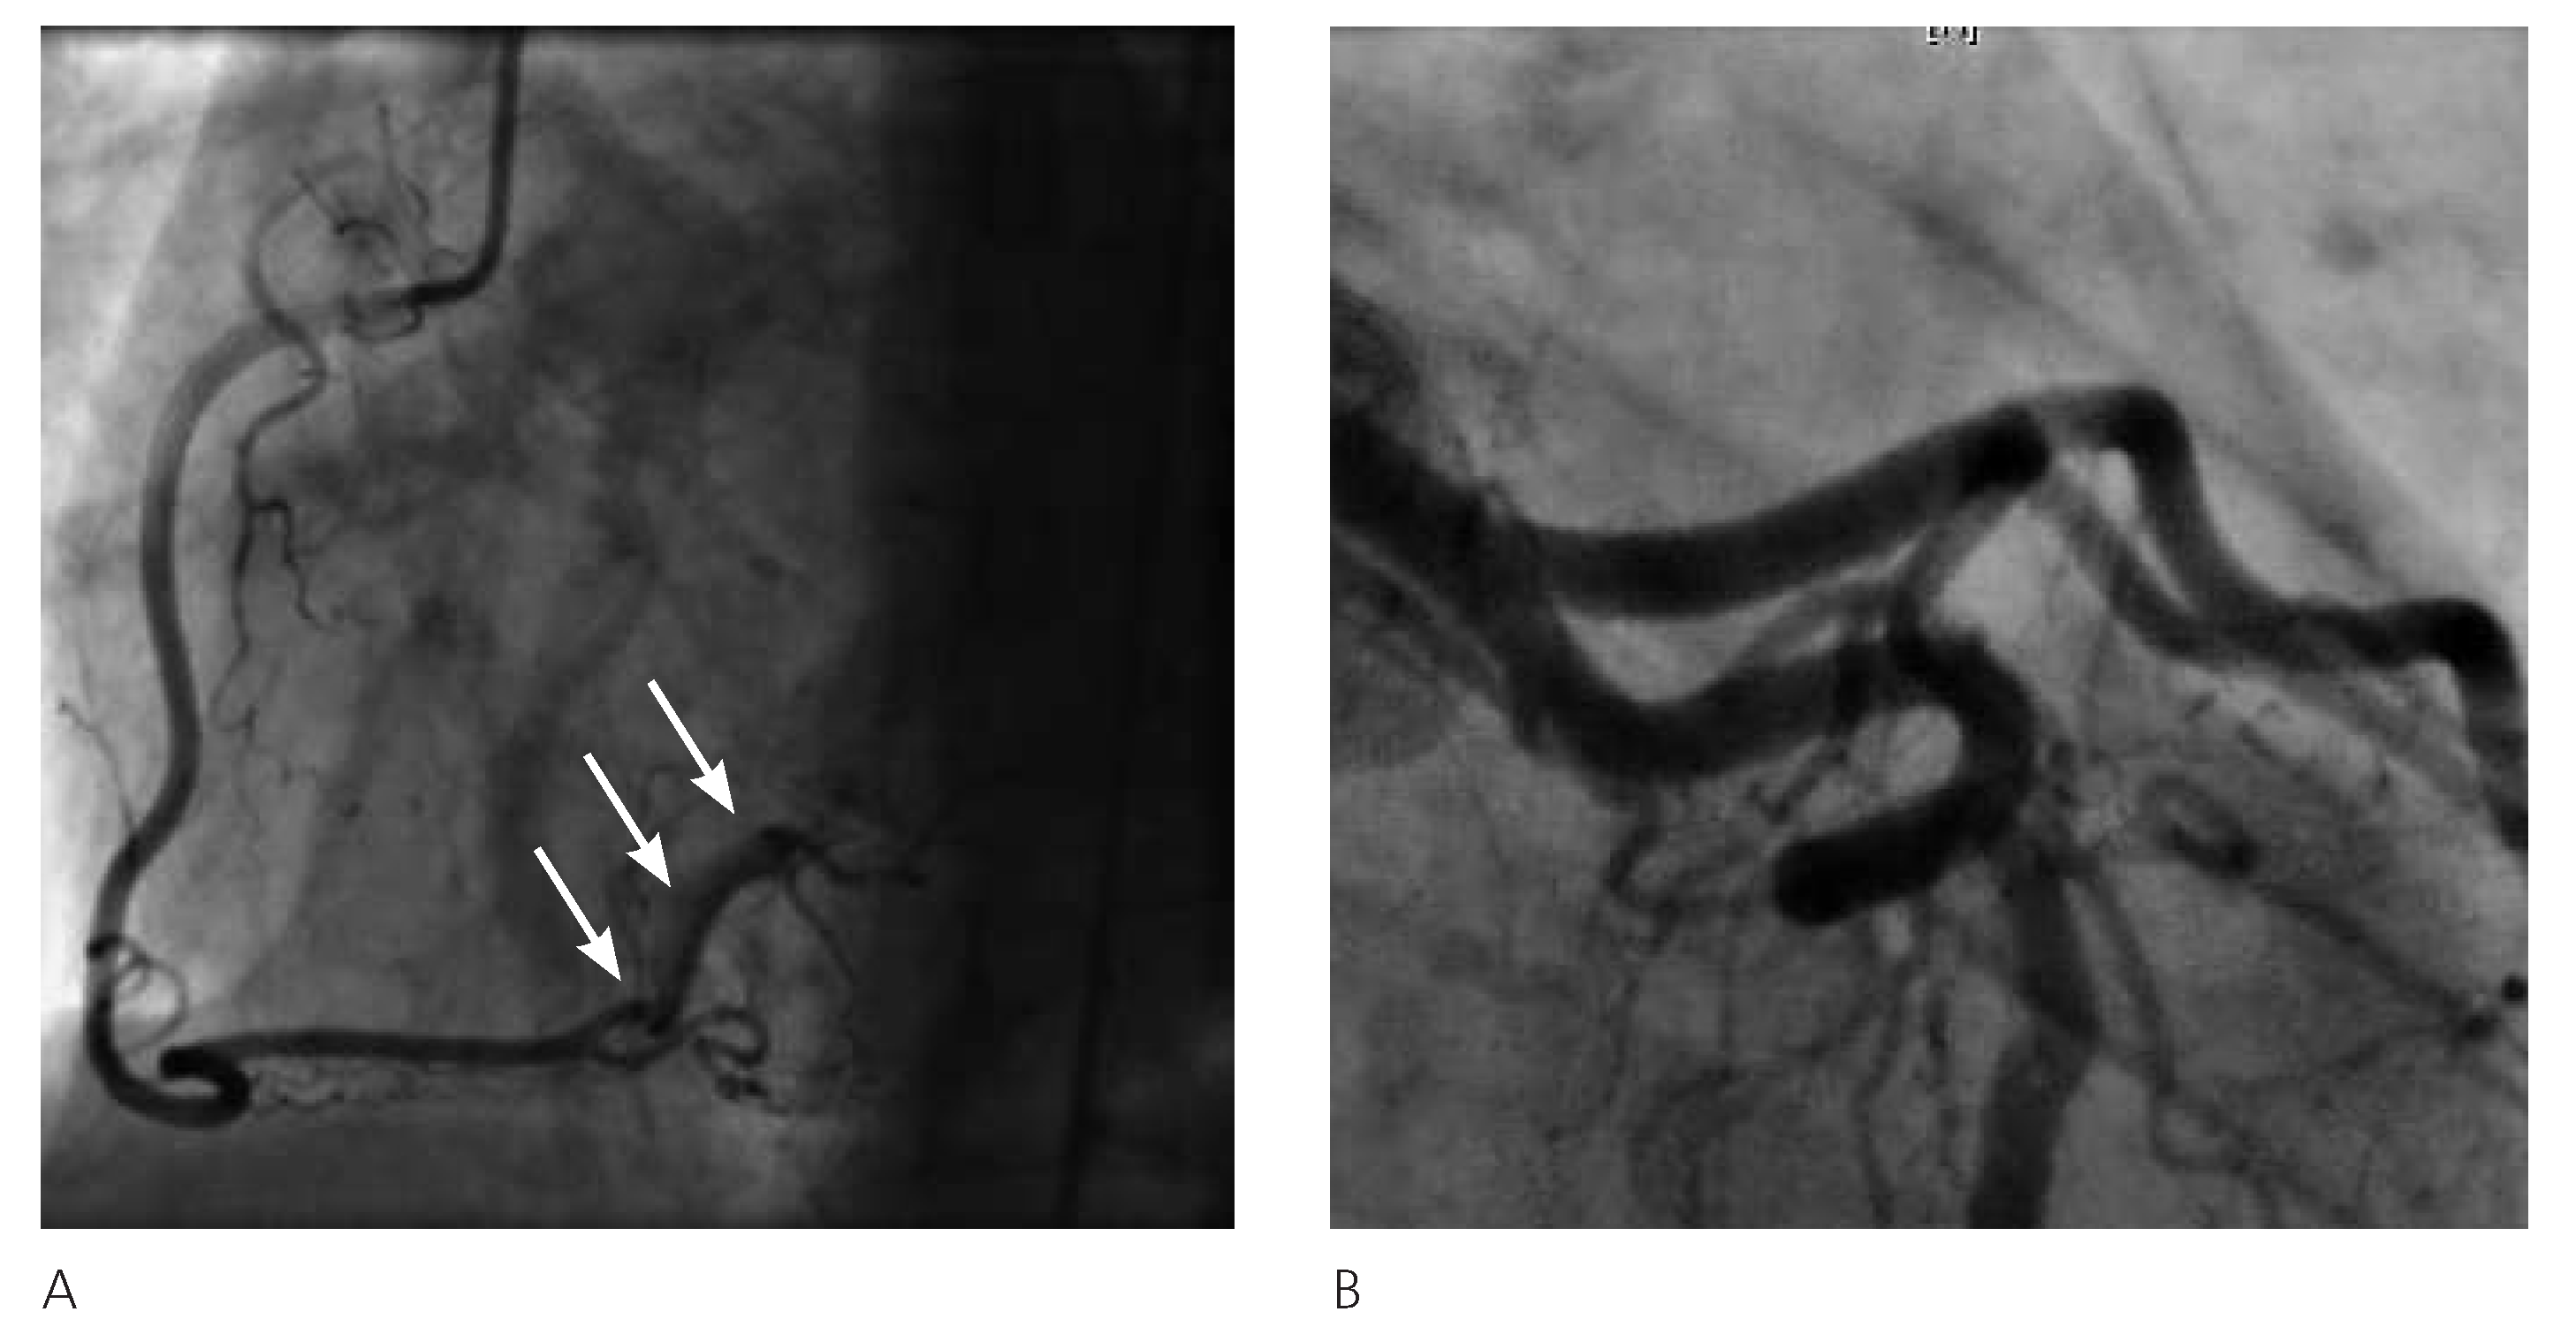

In November 2003, a 46-year-old woman, active smoker, with mild hypertension and a family history of cardiovascular disease, reported a sudden onset of pressurelike substernal chest pain, radiating to both arms: while being transported to the emergency department by ambulance, a cardiac arrest occurred with ventricular fibrillation as the first rhythm established. Cardiopulmonary resuscitation and direct current shock were performed and the return of spontaneous circulation was achieved. In the emergency department ECG showed regular sinus rhythm, 65 bpm, and ST depression in V2–V6 leads. The coronary angiography showed a long (around 25 mm) subtotal stenosis and narrowed vessel aspect (TIMI I) in the middle part of the tortuous LCx, with a small radiolucent defect in the proximal segment of the lesion, suggestive features of spontaneous dissection, without any other detectable coronary lesion. The patient underwent percutaneous coronary intervention (PCI) and three drug-eluting stents (Taxus-paclitaxel) were successfully implanted (Figure 1), resulting in restoration of TIMI III flow and resolution of symptoms. The patient improved and was discharged on double antiplatelet therapy for twelve months (Aspirin® and clopidogrel), beta-blocker and statin. Follow-up coronary angiography at three months demonstrated patency of the stents, without evidence of residual disease, and her medical treatment was confirmed. Thirty-four months later, in August 2006, the patient was admitted with unstable angina, positive troponin and T-wave inversion in precordial leads (V2–V5). The coronary angiography showed a fresh and long (>20 mm) dissection of the distal RCA propagating to the posterior lateral branch without any sign of disease in the other vessels (Figure 2). Once again the proximal segment of the lesion presented a tiny radiolucent line. In light of the unfavourable location of the lesion, its extension, the small size of the target vessel, and the symptoms easily managed with nitrates, a conservative treatment was deemed necessary. The patient had a favourable clinical course and discharge occurred three days later, on aspirin and clopidogrel for 3 months, beta-blocker and statin. In the follow-up the patient remained almost asymptomatic. Forty-eight months later, in Au gust 2010, because of recurrence of chest pain and inconclusive Echo-stress test, a new coronary angio graphy was performed. It showed a spontaneous recanalisation of the previously dissected RCA and posterior lateral branch, with a small persisting lesion (Figure 3); no sign of injury was found in the other vessels. Aspirin was confirmed at discharge. Since then, the patient is still on aspirin and beta-blocker, and completely asymptomatic at the follow-ups, last one performed in February 2014.

Figure 3. August 2010 coronary angiography. A. RCA spontaneous recanalisation with a small persisting lesion on the posterior lateral branch (arrows). B. Normal LAD and LCx artery with patency of the previous stent on LCx.